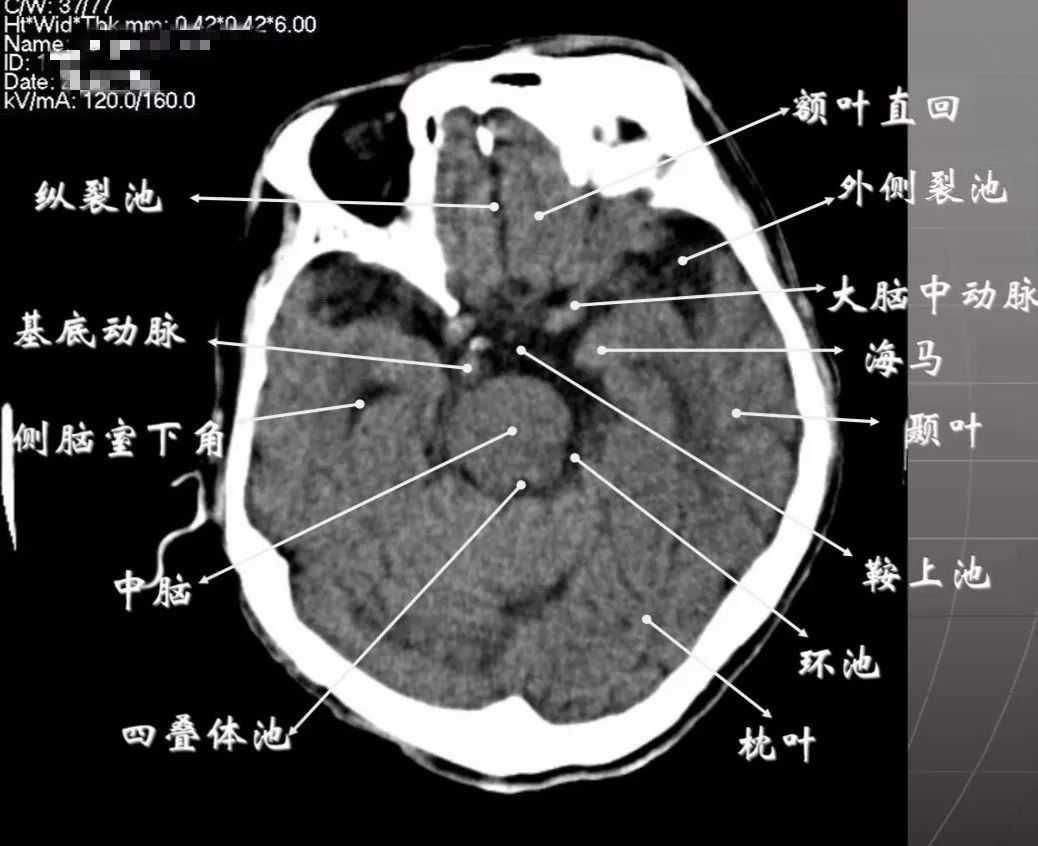

3、第三脑室下部层面显示侧脑室前角的下部:

前方——额叶;外侧——尾状核头部;后方中线处——第三脑室,其两侧连接丘脑。

颅后窝:

“Y”字形或“V”字形的小脑幕,幕下结构在内侧(小脑上蚓部),幕上结构在外侧(枕叶)。

四叠体池:

位于小脑蚓部前方。